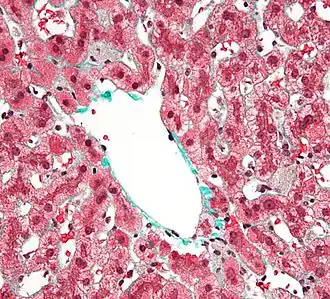

Кле́тки Ку́пфера — специализированные клетки, располагающиеся в люмене (внутреннем пространстве) синусоид печени и прикрепленные к синусоидальным эндотелиальным клеткам, образующим стенки кровеносных сосудов. Клетки Купфера — наиболее многочисленные резидентные макрофаги в печени человека, они входят в состав системы мононуклеарных макрофагов (ретикуло-эндотелиальной системы). Через воротную вену в печень из пищеварительного тракта поступают кишечные бактерии, бактериальные эндотоксины, которые в печени первым делом сталкиваются с клетками Купфера, образующими первую линию иммунной защиты печени. Нарушения функционирования клеток Купфера сопровождают многие заболевания печени, такие как алкогольная болезнь печени, вирусные гепатиты, внутрипечёночный холестаз, стеатогепатит, цирроз печени, а также при отторжении трансплантата печеночной ткани[2][3].

Клетки Купфера имеют амёбоидную форму и прикреплены к синусоидальным эндотелиальным клеткам. На поверхности клеток Купфера имеются микроворсинки, псевдоподии и ламеллоподии, расположенные во всех направлениях. Микроворсинки и псевдоподии задействованы в поглощении частиц. В цитоплазме клеток Купфера располагаются рибосомы, аппарат Гольджи, эндоплазматический ретикулум (в особенности, шероховатый), центриоли, микротрубочки и микрофиламенты. Ядро яйцевидное, может быть подразделено на доли. В органеллах клеток Купфера присутствует пероксидазная активность. Клетки Купфера локализованы и в центрилобулярной, и в перипортальной части долек печени, однако их функции в этих регионах различны. Перипортальные клетки Купфера более крупные, содержат больше лизосом и более активны в плане фагоцитоза, а центрилобулярные клетки Купферы специализированы на генерации супероксид-радикала. Внутри клеток Купфера имеются скэвенджер-рецепторы SR-AI/II. Они участвуют в распознавании и связывании липида A в составе молекул липополисахарида и липотейхоевых кислот. Липополисахарид является эндотоксином, входящим в состав клеточных стенок грамотрицательных бактерий, а липотейхоевые кислоты присутствуют в клеточных стенках грамположительных бактерий[4].